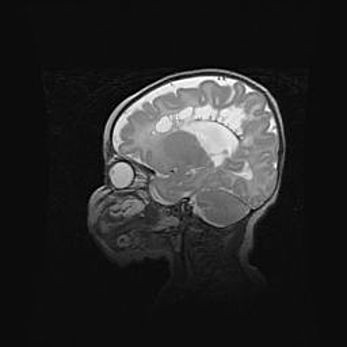

мрт снимки

Ниже представлена  галерея МРТ снимков, полученных с применением LMT неонатальных матричных РЧ катушек. Также каждая группа МРТ снимков сопровождается информацией о пациенте (диагноз, возраст, вес, пол, срок гестации) и краткой сопроводительной расшифровкой диагноза.

Церебральная ишемия II.

Возраст: 5 дней

Вес: 3400 г

Пол: женский

Окружность головы: 35 см

Срок гестации: 39 недель

Церебральная ишемия – это заболевание, характеризующееся недостаточностью (гипоксией) либо полным прекращением (аноксией) снабжения мозга кислородом по причине закупорки одного или нескольких сосудов. Это приводит к  что метаболическим расстройствам различной степени тяжести в тканях головного мозга, развитию коагуляционных некрозов и гибели нейронов.